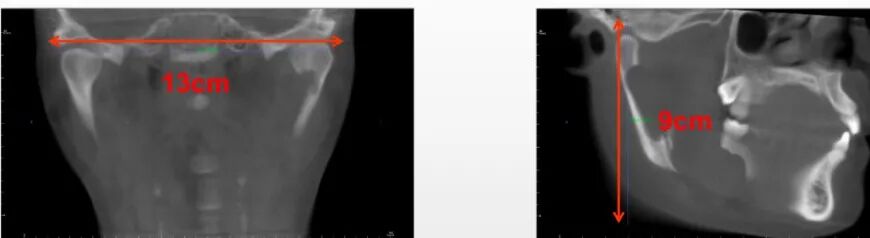

亚洲人左右颞下颌关节远中点距离通常在12.5cm左右,但因为颞下颌关节通常不在成像圆柱体的直径上,所以需要至少13cm的水平直径范围才能将左右颞下颌关节的全部解剖结构囊括在同一个CT影像上,而考虑到极个别患者的个体差异和摆位的误差,菲森选择了直径:

14cm的视野范围以确保万无一失;

同时,为了满足下颌下缘到颞下颌关节垂直距离通常在9cm的亚洲人体质,菲森特意选取了10cm的高度范围,以保证单次投照即可获得上颌窦全部和颞下颌关节全部。